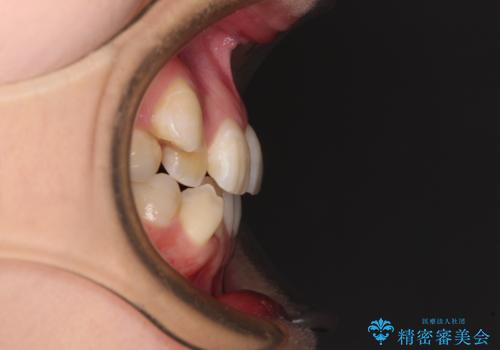

- 上下の八重歯と前歯のデコボコを気にして来院された患者様です。

右上と左下の八重歯が特に著しく、上顎正中が右側にシフトしていました。

デコボコが強いため小臼歯4本を抜歯し、上顎正中を左側に移動させるために補助装置を使用して、ワイヤー装置にて矯正治療を行うこととしました。